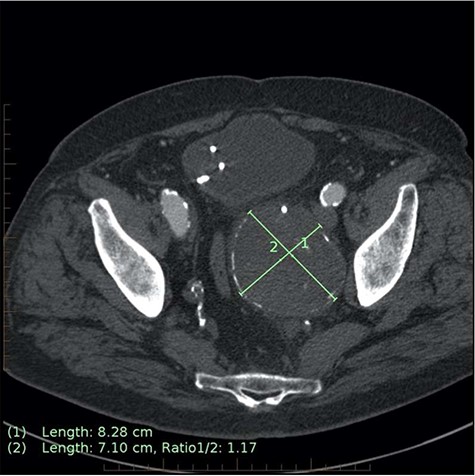

Axial CT image on 6-month follow-up demonstrating expansion of the IIAA by 7 mm, now measuring 83 × 71 mm axially (previously 76 × 62 mm).